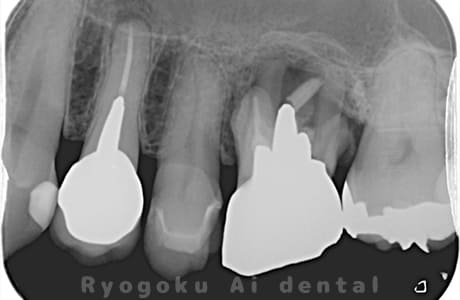

Case12

- 左下7番歯牙破折

-

- 治療内容

- インプラント治療

- 治療費用

- 約600,000円

左下の奥歯が痛いとのことでご来院された患者様です。歯が完全に割れており、保存が不可能であったため、抜歯を行い、その際に骨に変わるお薬を入れ、十分な治癒を待ってからインプラント治療を行いました。経過良好で、大変満足されました。

<リスク・副作用>

治療後、痛みや違和感、出血、腫れなどが出る事があります。喫煙者、糖尿病などの方の場合、歯が生着しない場合があります。